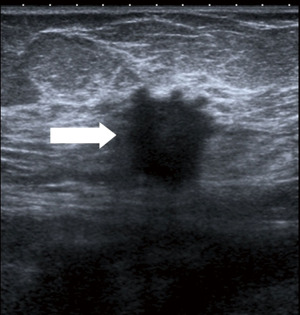

Figure 10 Mammography of the left breast in cranio-caudal view (A) with architectural distortion (arrow). The distortion is more visible in DBT (B) (arrow). Ultrasound (C) reveals subtle finding of irregular area of decreased echogenicity (arrow). MRI (D) shows extensive area of non-mass-like enhancement in the whole lateral part of the breast (arrow). DBT, digital breast tomosynthesis; MRI, magnetic resonance imaging. - Diagnostic assessment, a patient of 45 years of age with a palpable lump on the right side for 2 months. In mammography with higher proportion of fibroglandular tissue (category C) several areas of increased density with irregular margins and architectural distortions are visible. Ultrasound confirms more than one lesion. MRI demonstrates a large area of enhancement up to 7 cm (Figure 11).

Figure 11 Mammography of the right breast in medio-lateral-oblique (A) and cranio-caudal view (B) with multiple densities with irregular margins and architectural distortions (arrows). Ultrasound (C) shows more than two hypoechoic lesions of suspicious features. In MRI (D) an extensive area of tumour involvement is revealed. MRI, magnetic resonance imaging. - A patient of 50 years of age evaluated for enlarged lymph nodes in the axilla. Mammography and ultrasound show enlarged pathological lymph nodes in the axilla, otherwise no pathological finding in the breast on initial evaluation despite the low mammographic density. The largest lymph node is biopsied proving metastatic invasive carcinoma NST of breast origin. MRI is indicated to search for an occult lesion in the breast. MRI shows the enlarged lymph nodes and a small lesion in the right breast in upper outer quadrant. A second-look, targeted ultrasound with the knowledge of the location of the lesion is performed to reveal a small suspicious lesion, which is subsequently verified as the primary tumour in the breast (Figure 12).